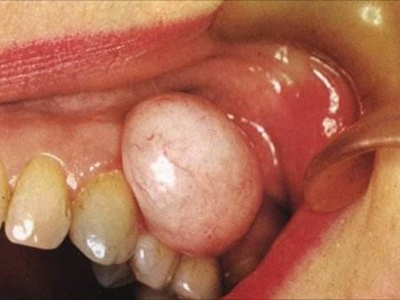

牙龈瘤多发于女性,以青年及中年人为常见,多发生于牙龈乳头部,位于唇、颊侧者较舌、腭侧者多,最常见的部位是前磨牙区。肿块较局限,呈圆形或椭圆形,有时呈分叶状,大小不一,直径由几毫米至数厘米。

肿块有的有蒂,如息肉状;有的无蒂,基底宽广,生长较慢,但在女性妊娠期间可能迅速增大。较大的肿块可以遮盖一部分牙及牙槽突,表面可见牙压痕,易被咬伤而发生溃疡,伴发感染。随着肿块的增长,牙槽骨壁逐渐被破坏,牙可能发生松动、移位。